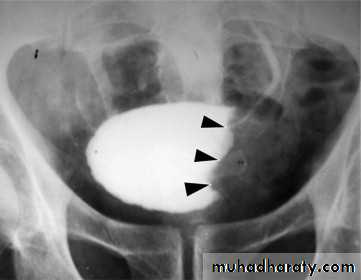

Schistosomiasis

Infestation by s.hematobiumCalcification is most important feature, mainly in bladder & lower ureters , but may involve whole ureters .

In early stage inflammation may cause cobble stone appearance.

Bladder capacity not affected.

Ddx of bladder calcification :

1. schistosomiasis .2. tumor , TB …